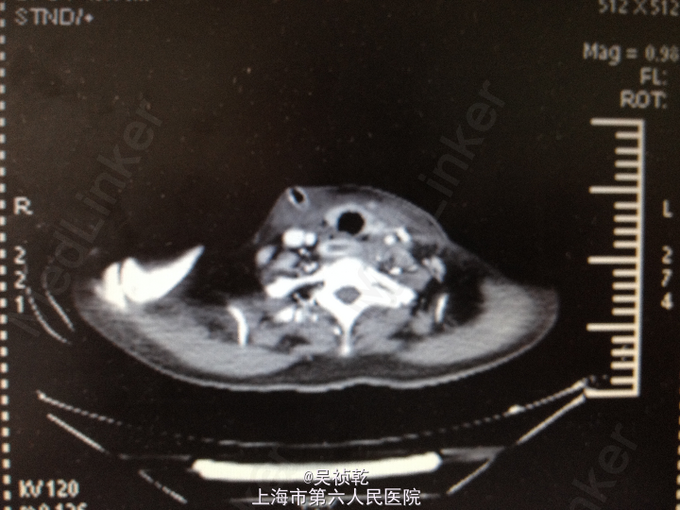

查体:神志清醒,呼吸稍促,推入病房,发育正常,营养良好,自主体位。皮肤粘膜:无黄染,无瘀点瘀斑,无贫血貌,无肝掌,无蜘蛛痣。淋巴结:全身浅表淋巴结可触及肿大。双侧颌下淋巴结肿大,左侧颈部肿大,皮肤红肿,皮温偏高,局部有波动感。头颈部:无头颅畸形,无巩膜黄染,无结膜苍白 ,口唇无紫绀,无扁桃体肿大。颈软,气管居中,甲状腺无肿大,无颈静脉怒张。胸部:胸廓无畸形,心率105次/分, 节律齐,无杂音,两肺呼吸音清,未及啰音。腹部:腹部平坦,腹壁柔软,全腹无压痛、无反跳痛,肝脏肋下未触及,脾肋下未触及,肝区无叩击痛,肾区无叩击痛。无移动性浊音,肠鸣音正常。肛门、直肠及外生殖器: 正常。脊柱与四肢:脊柱无畸形,四肢无畸形,四肢活动自如。神经系统:生理反射存在,病理反射未引出。 辅检:2015-4-8 血气检验报告:二氧化碳分压 34.7 mmHg ↓,氧分压 60.9 mmHg ↓,氧饱和度 91.8 % ↓。门诊化验检验报告:凝血酶原时间 13.1 秒 ,国际标准化比率 1.19 ↑,部分凝血活酶时间 30.4 秒 ,D二聚体 1.13 mg/L FEU ↑,纤维蛋白(原)降解产物 6.4 mg/L ↑。 生化检验报告:肌钙蛋白-I 0.013 ,CKMB 1.4 ug/L ,肌红蛋白 28.6 ug/L 。 生化检验报告:血清钾(干式) 4.5 mmol/L ,血清钠(干式) 137 mmol/L ↓,血清氯(干式) 94 mmol/L ↓,总蛋白(干式) 66 g/L ,白蛋白(干式) 32 g/L ↓,谷丙转氨酶(干式) 26 U/L ,谷草转氨酶(干式) 16 U/L ,γ-谷氨酰酶(干式) 19 U/L ,碱性磷酸酶(干式) 103 U/L ,总胆红素(干式) 16 μmol/L ,尿素(干式) 7.5 mmol/L ↑,肌酐(干式) 67 μmol/L ,尿酸(干式) 154 μmol/L ↓,淀粉酶(干式) <30 U/L ↓,血糖(干式) 22.0 mmol/L ↑,B型钠尿肽前体(proBNP) 199.80 ng/L ↑。 2015-4-9 血常规检验报告:白细胞 13.2 X10^9/L ↑,红细胞 3.76 X10^12/L ↓,血红蛋白 125 g/L ↓,细胞比积 35.8 % ↓,血小板 261 X10^9/L ,淋巴细胞百分比 4.7 % ↓,中性细胞百分比 84.4 % ↑。糖尿病医学中心检验报告:糖化血红蛋白 12.40 % ↑。 颈部超声示:双侧颌下淋巴结肿大,左侧颈后软组织结构紊乱,内混合回声及肿大淋巴结,考虑炎性改变可能,建议治疗后复查。 颈部CT:1.咽后间隙、左侧咽旁间隙及颈动脉鞘软组织明显肿胀、渗出,颈部多发肿大淋巴结,考虑炎症可能大,请结合临床并门诊增强CT评估。2.左侧甲状腺小结节可能,请结合临床,必要时随访。 2015-4-9 颈部增强CT示:颈部及胸腔纵隔脓肿形成。 2015-4-8引流分泌物培养结果: 肺炎克雷伯菌。

患者入院时诊断为:1.左颈部脓肿,颈部软组织感染,纵膈脓肿形成。2.糖尿病。 入院后予对症处理:1.加强抗感染,予万古霉素+磷霉素联合。2.床边行脓肿切开引流,引流液送培养。2、予吸氧、禁食、营养支持等对症治疗。3.病情危重,告知家属相关风险,予告病危。4.进一步完善颈部及胸部增强CT,病请五官科会诊。 2015.04.09CT提示颈部,咽后壁及胸腔纵隔脓肿形成,故请五官科及胸外科会诊,会诊意见为:手术切开引流。故于4.9全麻下行颈部脓肿清创引流术。 手术过程:患者取仰卧位,肩部垫高,全麻达成后,常规消毒铺巾。在胸骨切迹上约两横指处顺皮纹方向作弧形领式切口,长约8cm。依次切开皮肤、皮下组织和颈阔肌。游离颈阔肌深面间隙,在其深面用电刀分离皮瓣,上至甲状软骨切迹,下至胸骨切迹,两侧越过胸锁乳突肌前缘。分离右侧胸锁乳突肌,分离至咽后间隙,咽后间隙内见大量脓液,予双氧水,稀碘伏水,及生理盐水彻底冲洗脓腔。术中请胸外科会诊认为目前上纵隔脓肿暂无需处理。左右各置一根颈部引流管;仔细止血;清点器械无误后,缝合皮下及皮肤层。术中出血少未输血,术程顺利,病人安返。 术后诊断:1.左颈部脓肿,颈部软组织感染,纵膈脓肿形成。2.糖尿病。3.全身感染症状。4.吞咽困难。 术后结合药敏结果,继续予万古霉素+磷霉素联合抗炎,引流管予生理盐水持续冲洗引流,目前引流液不多,术后一周复查CT见脓肿明显缩小,纵膈脓肿有所缩小,目前治疗方案:1.停用原抗菌方案,换用莫比沙星 0.4 qd 静滴,每次滴注90min;2.每3天复查血象,及时复查颈部CT,治疗5天后再评估,一般情况好可停药随访;3.糖尿病患者,注意血糖变化,监测心功能及肝肾功能。